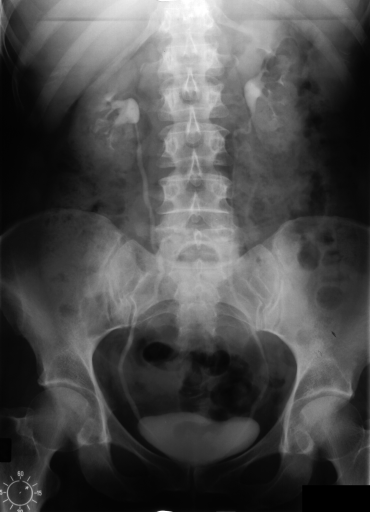

Figure 3 shows some samples images from IRMA dates along with their corresponding IRMA codes.